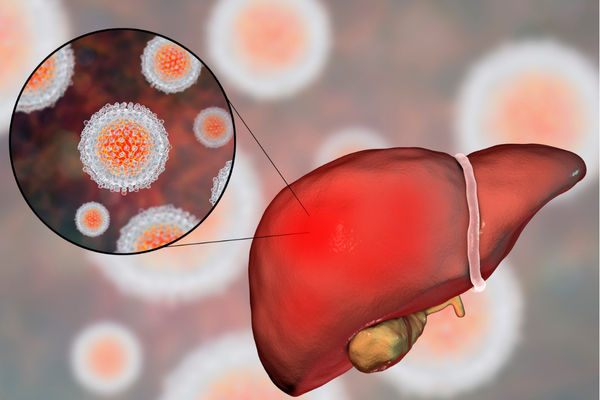

O Julho Amarelo é uma campanha nacional de conscientização e combate às hepatites virais, doenças silenciosas que atingem o fígado e que, se não forem diagnosticadas e tratadas precocemente, podem evoluir para quadros graves, como cirrose e câncer hepático.

As hepatites virais são inflamações no fígado causadas por diferentes vírus, os mais comuns são os tipos A, B, C, D e E. Cada tipo tem sua forma de transmissão, gravidade e tratamento. Algumas são curáveis, outras podem ser controladas, mas todas exigem acompanhamento médico especializado.